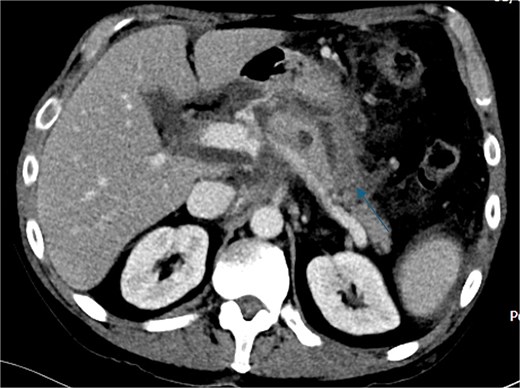

Despite the absence of abdominal symptoms, a computed tomography of the abdomen and pelvis (CTAP) was performed due to markedly elevated lipase levels. The CTAP (Figs 3–5) revealed evidence of acute pancreatitis (Fig. 5, arrow), with a complex peripancreatic fluid collection (Fig. 3, arrow). Additionally, a focal thrombus was observed within the portal venous confluence (Fig. 4, arrow). Further ultrasound of the gallbladder was negative for gallstones (Fig. 6), ruling out gallstone-induced pancreatitis.

CTAP coronal view; focal thrombus within the portal venous confluence (arrow).